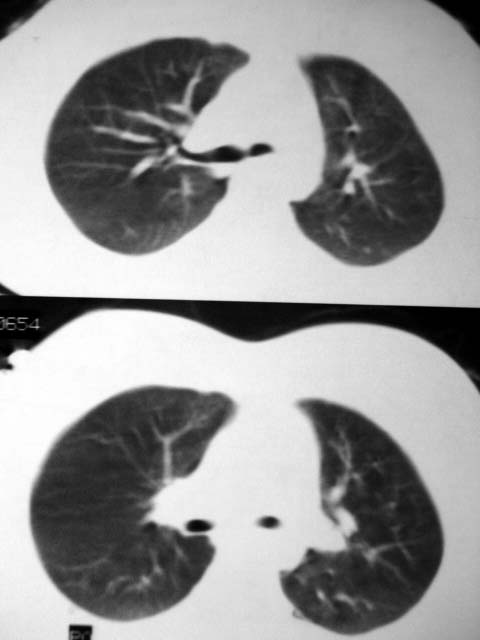

标题: CT12463:女,19岁,炎性假瘤?结核球? [打印本页]

女,19岁,体检时发现。炎性假瘤?结核球?

病灶肺纵比较大,边缘平直,周围无卫星灶,考虑炎症。建议抗炎治疗后复查。

病灶片状改变,呈钱币样,周围炎性反应明显,考虑球形肺炎可能性大,球形肺炎与炎性假瘤鉴别的重要一点是,炎性假瘤抗炎治疗不会明显改变。

首先要说ct机太差,片子质量不佳,一定是2秒以上机器的作品!其次ct技师需进一步培训,象这种情况就应该针对病灶部位做薄层或高分辨扫描。不过从上传影像看,患者年轻、病灶周围没卫星灶倒支持炎性假瘤诊断,不过象这种部位也有可能是叶间包裹性积液可能。只是ct机太、太差,很难诊断,如一秒机扫描出来90%可直接诊断,有必要时可结合矢状位三维重建。所以要我说建议患者在亚秒(至少是1秒)机上重扫十分有利于正确诊断。